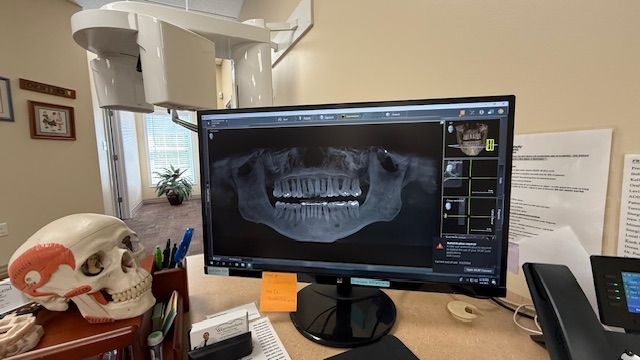

At our office, we’re proud to be one of the only dental practices in the region equipped with advanced Panoramic and Cone-Beam Computerized Tomography (CBCT) technology. Think of it like an MRI for your head, neck, and mouth—this powerful tool gives us detailed 3D images from multiple angles and “slices,” allowing us to detect issues, identify pathology, and deliver far more accurate diagnoses than traditional imaging. It’s just one of the ways we’re committed to providing the highest level of care.

The panoramic x-ray machine rotates around your head, capturing multiple images of your teeth, jawbone, sinuses, and surrounding soft tissues in one single scan. This creates a complete, 2D image that gives Dr. Westmoreland an enhanced view of your oral health. The entire process is quick and non-invasive, and you will only need to stand still for a few moments while the machine takes the image.